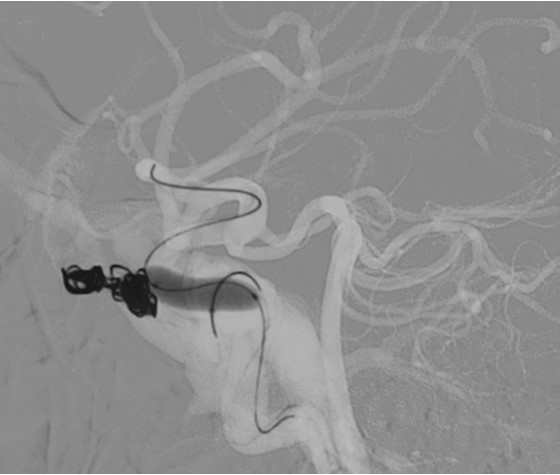

10여 년 전부터 뒷목 통증과 함께 오심, 구토 증세가 간헐적으로 있었으며 2010년 2월 질식분만으로 분만하며 대량 출혈이 있었다고 한다. 이후 기억력 저하가 있었으며 이때부터 시력 저하를 주소로 안과 진료를 받았으며, 두통과 복시 동반되어 편두통이라고 듣고 약물 치료했다고 한다. 내원 한달 전 목이 과신전되는 일이 있었으며 목 뒤가 뻐근하며 박동성 이명이 좌측에서 들렸고 두통, 좌측 눈꺼풀 쳐짐과 충혈이 같이 생겼으며 복시가 심하였다고 하였다. 환자는 증상이 생긴 후 좌측 목을 누르면 이명이 호전되는 양상이 있어서 스스로 좌측 목을 누르고 있었다고 한다. 외부병원 내원하여 시행한 뇌전산단층촬영, 진단적 뇌동맥 혈관조영촬영상 좌측 경동맥정맥동루가 발견되었다. 환자는 경동맥 정맥동루의 코일 색전술을 시행하였으며 (Fig. 1A) 이후 4시간이 경과한 뒤 우측 하지의 심한 통증을 호소하였다.

Fig. 1. A

A 29 year old fanale witii Ehlers-Dan los syndrome.

A. Coil embolization was performed for carotid-cavernous fistula.